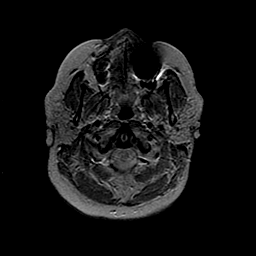

MR Study #2 -- Slice #4